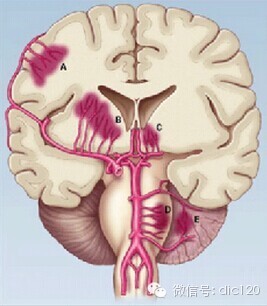

高血压性脑出血是指非外伤性脑实质内的自发性出血,多发于50岁以上高血压动脉硬化病人,主要病因是高血压伴发的小动脉病变,常见于壳核、外囊、丘脑、内囊、大脑半球白质内(见下图)

A 皮质动脉穿通支---脑叶出血 B 外侧纹状体动脉---壳核出血

C 丘脑穿通动脉------丘脑出血 D 旁正中动脉---------脑桥出血

E SCA和AICA的分支------小脑出血(齿状核)